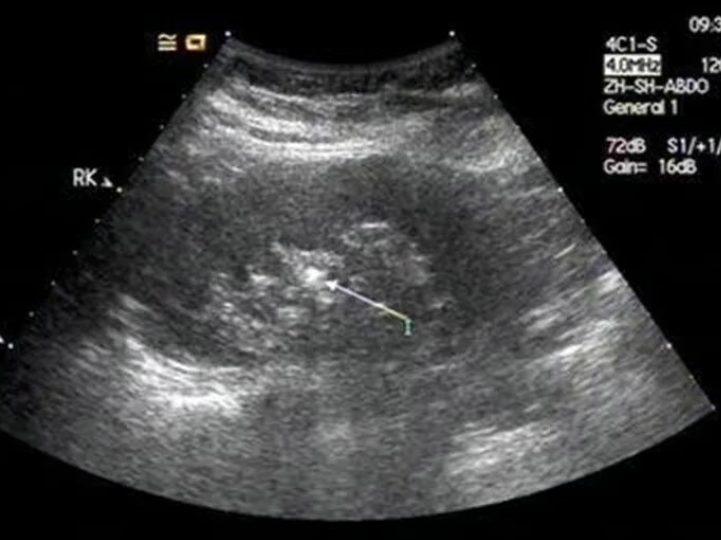

无锡嘉仕恒信医院作为结石特色专科,优势明显。它设立了 24 小时排石绿色通道,无论何时患者因结石疼痛前来就诊,都能快速得到救治。医院年平均处理数千例结石患者,其中三分之一发生在夜间时段,真正做到 “结石痛不隔夜”。在技术上,医院采用先进的经尿道软镜钬激光碎石术,可视下精准锁定结石,快速取石,术后 24 小时患者恢复良好。此外,还拥有无创 / 微创碎石等多种技术,如体外冲击波碎石(ESWL)无需手术、无伤口,轻松碎结石;输尿管镜 / 经皮肾镜取石等微创技术,精准清除顽固结石。医院的专业结石团队成员大多具备 10 年以上临床经验,且引进德国、瑞士先进碎石设备,精准定位结石位置,减少对患者身体的损伤,众多康复患者对其治疗效果和服务给予高度评价。